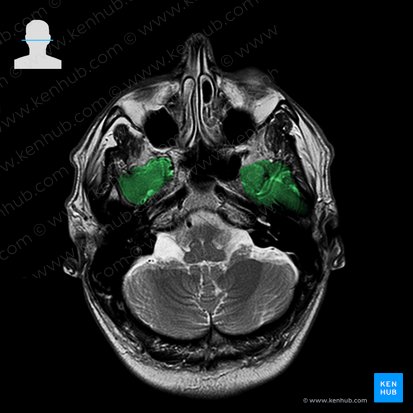

Pars petrosa (Felsenbein) |

Pyramidenförmiger, mittlerer Teil des Os temporale Schützt das innere Gehör- und Gleichgewichtsorgan Besitzt zahlreiche Öffnungen (Canalis caroticus, Foramen jugulare, Processus mastoideus) |

Pars petrosa

Die Pars petrosa (Felsenbein) ist der pyramidenförmige, mittlere Teil des Os temporale, der die mittlere von der vorderen Schädelgrube trennt. Sie ist extrem stabil und schützt das innere Gehör- und Gleichgewichtsorgan. Der innere Gehörgang (Meatus acusticus internus) liegt an der Facies posterior und führt zum äußeren Gehörgang.

Die Facies inferior enthält zahlreiche Öffnungen wie den Canalis caroticus (→ A. carotis interna) und das Foramen jugulare (→ V. jugularis interna, N. glossopharyngeus, N. accessorius, N. vagus). Der hinterste Bereich der Pars petrosa wird vom Processus mastoideus (Warzenfortsatz) gebildet, der mit Cellulae mastoideae (Mastoidzellen) gefüllt und mit Schleimhaut ausgekleidet ist. Der Processus mastoideus dient als Ursprung des Musculus auricularis posterior.